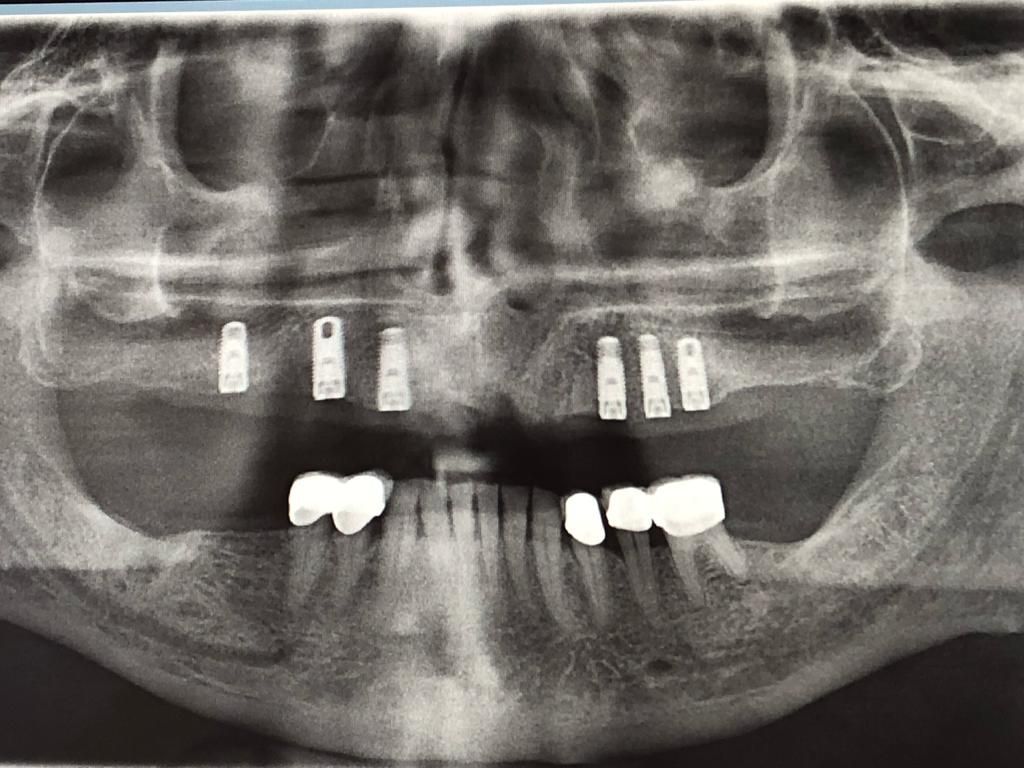

Ogni fase del trattamento, dalla valutazione iniziale alla pianificazione precisa con ortopanoramica digitale, fino all'inserimento dell'impianto e all'applicazione della protesi definitiva, è curata con la massima attenzione per assicurare il benessere e la soddisfazione dei nostri pazienti. Il nostro impegno è fornire cure personalizzate in un ambiente accogliente e professionale, aiutandoti a ritrovare un sorriso sano e radioso.